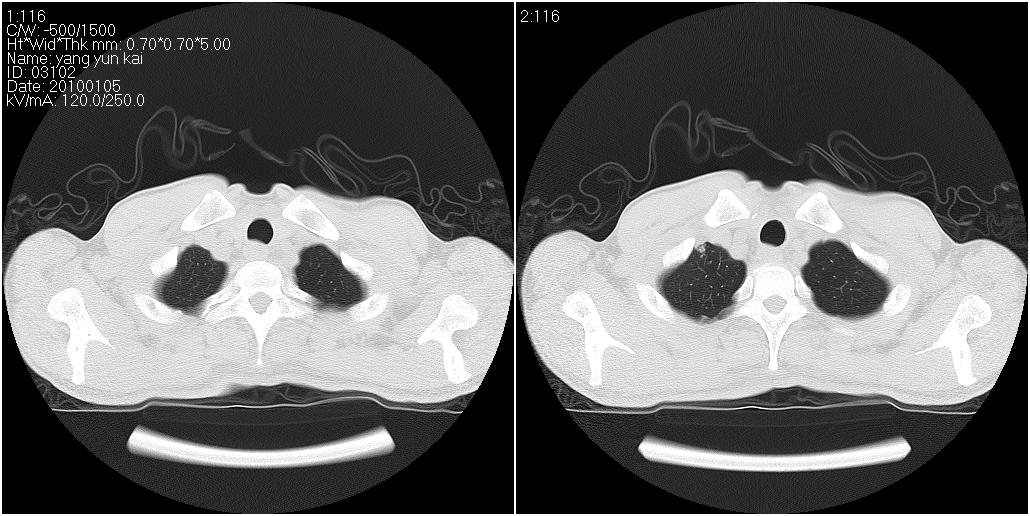

标题: CT23980:男性,47岁。近来咳痰、咳血,血沉增快(40左右),

男性,47岁。近来咳痰、咳血,血沉增快(40左右),痰中未检出结核杆菌。

两肺继发性肺结核并多发性结核球形成,部分病灶内空洞形成。

符合继发性结核表现部分空洞形成并播散